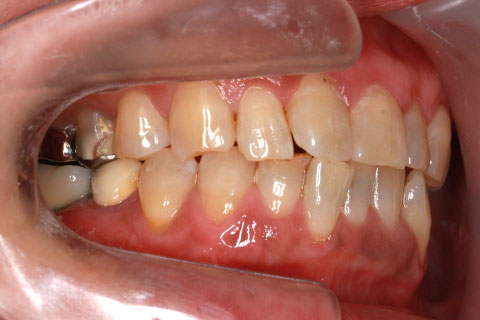

• オールセラミックの症例2

治療前

治療後

年齢・性別

45歳男性

治療期間

2ヶ月

抜歯

なし

治療費

70.4万円

備考

前歯8本の歯列不正によるセラミック治療

治療内容

歯質を削除し、セラミック冠をセメント合着

施術の副作用(リスク)

知覚過敏、歯髄炎、荷重負担